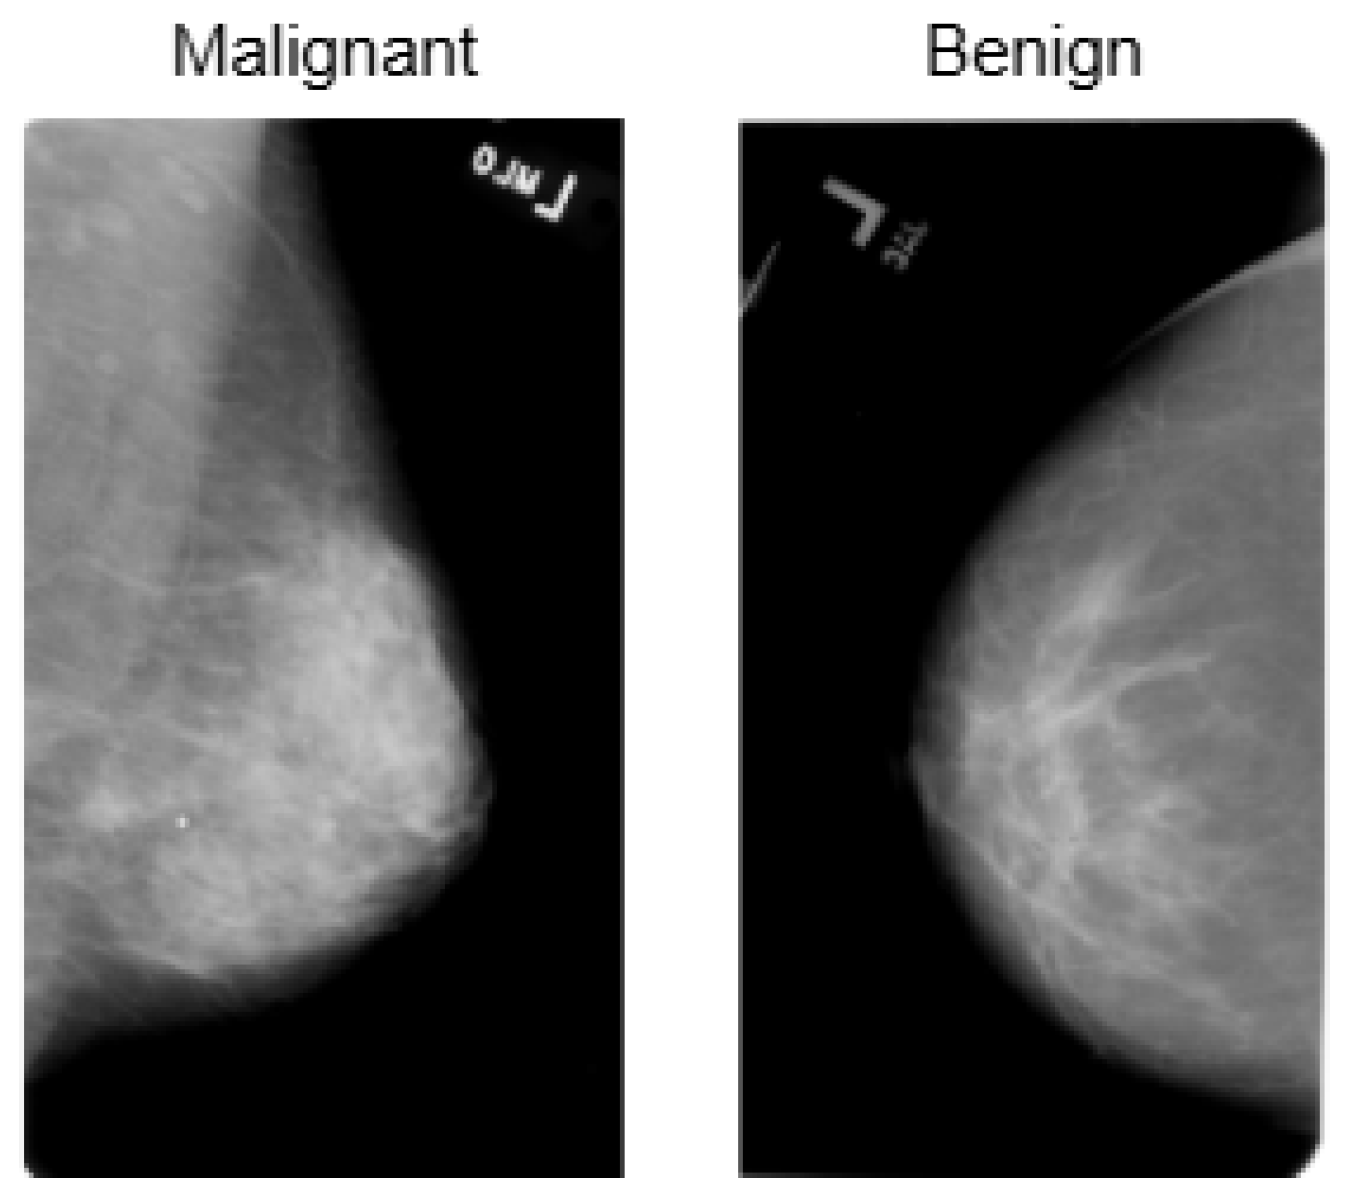

The INbreast dataset consists of 7632 full-field digital mammography (FFDM) images collected from 115 patients. Each image has been meticulously annotated by radiology experts to ensure high diagnostic accuracy. The dataset includes standard mammographic views—craniocaudal (CC) and mediolateral oblique (MLO)—for both breasts, although, in cases of mastectomy, only the remaining side is imaged. This dataset captures a variety of clinical scenarios, including screening, diagnostic, and follow-up procedures. For classification purposes, images are labeled as either benign or malignant. Benign cases encompass cysts, fibroadenomas, and calcifications, while malignant cases include tumors and suspicious lesions. What sets INbreast apart is its high-resolution imaging, acquired using a MammoNovation Siemens FFDM system with solid-state amorphous selenium detectors. The images are stored in DICOM format, featuring a resolution of 70 microns per pixel, with dimensions of either 3328 × 4084 or 2560 × 3328 pixels, depending on the compression plate used. Each image is accompanied by detailed XML-based annotations that provide information on lesion contours, types, biopsy results, and BI-RADS categories (3–6). Furthermore, the dataset includes patient metadata such as age, family history, BI-RADS assessments, and breast density classifications according to ACR standards. Figure 4 illustrates representative samples.

The CBIS-DDSM consists of 3086 high-resolution mammographic images collected from 892 patients. This dataset is designed to support tasks related to computer-aided detection and diagnosis, specifically focusing on distinguishing between benign and malignant abnormalities. It includes both full-field digital mammograms and cropped regions of interest (ROIs), allowing for precise localization and analysis of suspicious areas. The images are categorized into benign and malignant classes and cover a range of mammographic findings, such as masses, calcifications, and architectural distortions. Each image is annotated with details, including lesion contours, lesion types, and biopsy-confirmed pathology labels. Additionally, BI-RADS assessments and standard mammographic views are provided to ensure clinical consistency. All images are stored in DICOM format, with full-resolution images maintained at a 16-bit depth and cropped ROIs at an 8-bit depth. For preprocessing and compatibility with various models, the images were converted to grayscale PNG format while preserving their original bit depth. ROIs were resized to 598 × 598 pixels to retain pathological detail. Supplementary metadata includes patient demographics, BI-RADS categories, and descriptions of the lesions. Figure 5 presents representative samples from the dataset.